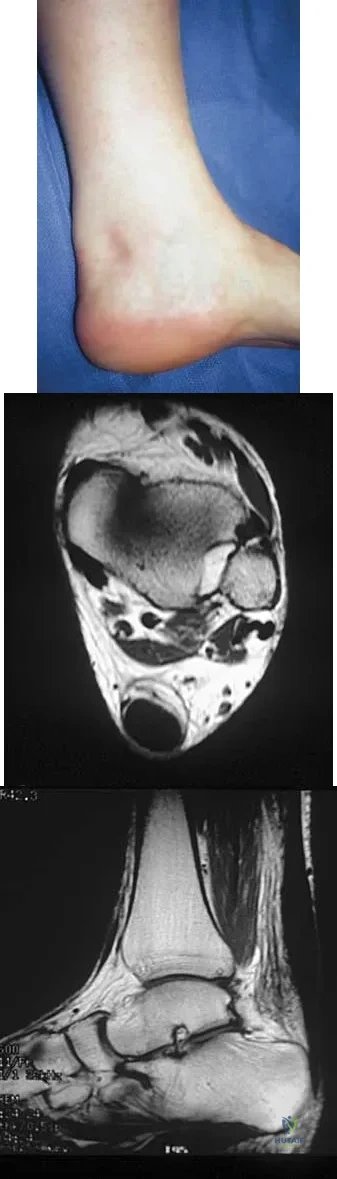

A 16-year-old girl has had pain and swelling along the medial arch of her left foot for the past 3 months. She also reports pain from shoe wear and while running. Nonsteroidal anti-inflammatory drugs have failed to provide relief. Radiographs are shown in Figures 40a through 40c. What is the next most appropriate step in management?